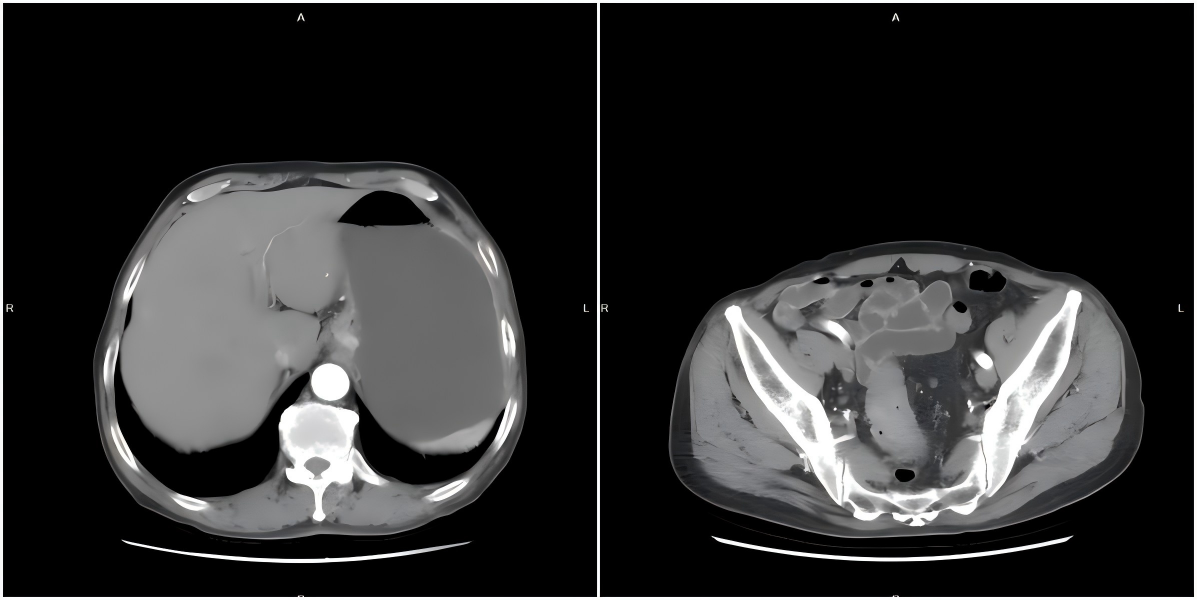

双源癌是指同一患者体内同时或先后出现两个互不关联的原发性恶性肿瘤。这两个肿瘤在组织学类型、起源部位及生物学行为上均独立存在,且排除转移或复发的可能。患者通过内镜及影像学检查诊断为贲门癌同时合并直肠上段癌,因贲门肿瘤位于上腹部,直肠肿瘤位于盆腔,两处肿瘤位置相距甚远,手术切口、术者站位及相关器械摆放位置均不同,手术复杂程度及手术难度均较高。

张晓峰主任组织全科人员进行术前讨论,综合患者心肺相关检查及肿瘤影像学的相关资料,分析手术中可能遇到的相关问题并逐一制定应对方案,最后制定腹腔镜胃癌根治+直肠癌根治术的手术方案。术中调整手术戳孔布局,兼顾胃癌根治及直肠癌根治的手术需要,成功完成近端胃根治+直肠癌根治术,手术用时5小时顺利结束。术后患者胃肠功能恢复良好,顺利出院。